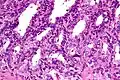

Microanatomy

The inner lining of the seminal vesicles (the epithelium) is made of a lining of interspersed column-shaped and cube-shaped cells.[8] There are varying descriptions of the lining as being pseudostratified and consisting of column-shaped cells only.[9] When viewed under a microscope, the cells are seen to have large bubbles in their interior. This is because their interior, called cytoplasm, contains lipid droplets involved in secretion during ejaculation.[8] The tissue of the seminal vesicles is full of glands, spaced irregularly.[8] As well as glands, the seminal vesicles contain smooth muscle and connective tissue.[8] This fibrous and muscular tissue surrounds the glands, helping to expel their contents.[3] The outer surface of the glands is covered in peritoneum.[3]

Low magnification micrograph of seminal vesicle. H&E stain.

Low magnification micrograph of seminal vesicle. H&E stain. -

High magnification micrograph of seminal vesicle. H&E stain.

High magnification micrograph of seminal vesicle. H&E stain.